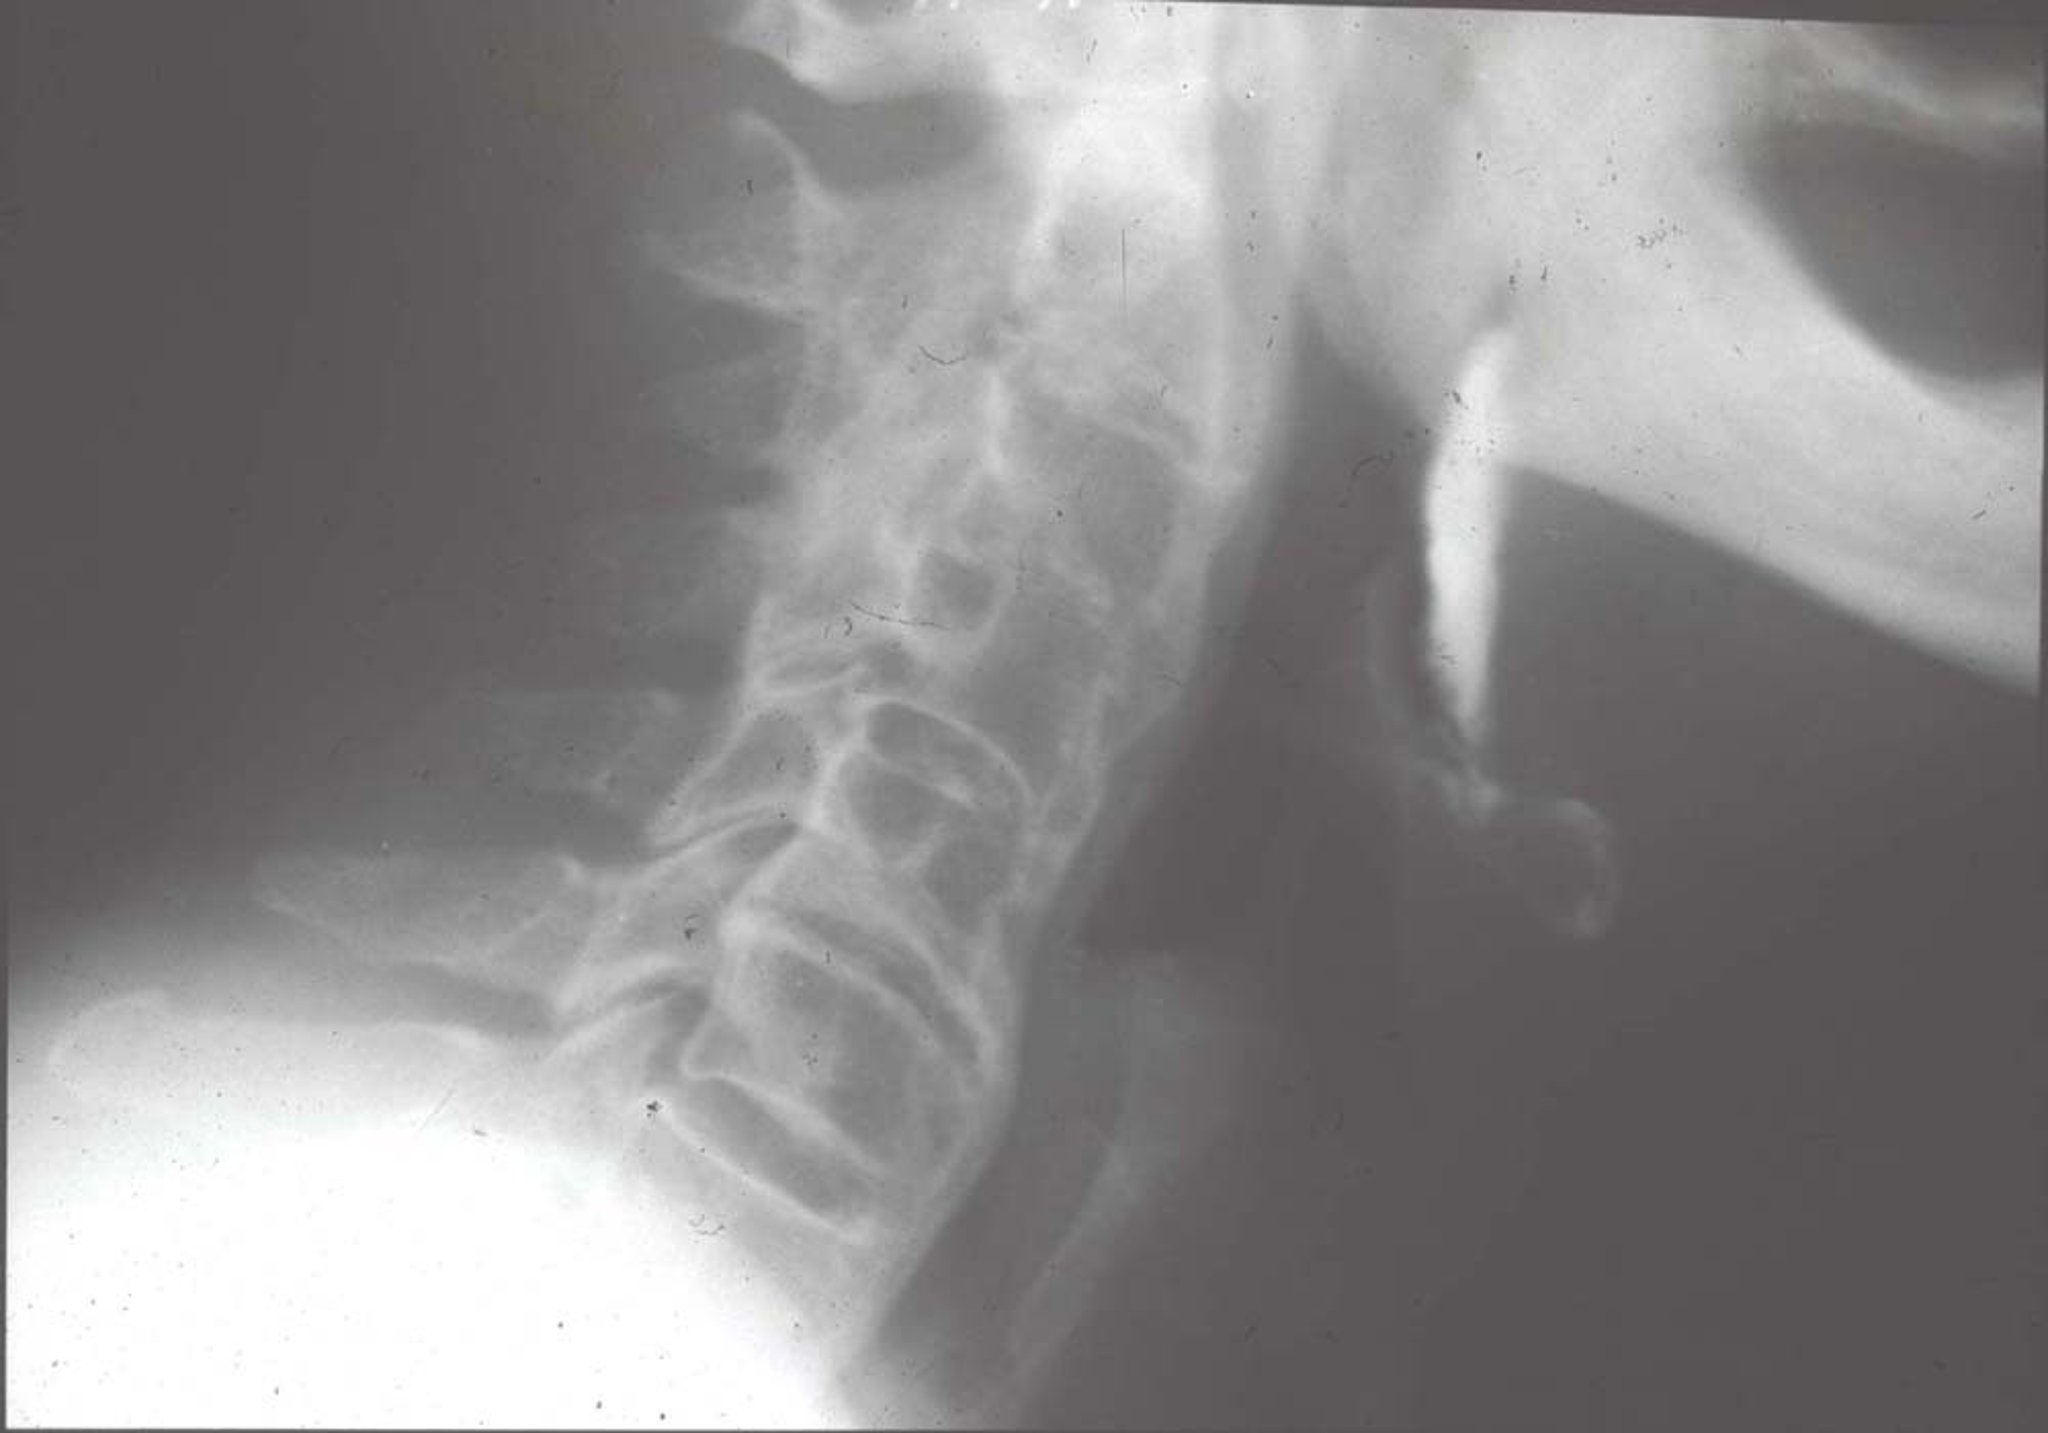

Diffuse Idiopathic Skeletal Hyperostosis (Radiograph)

Characteristic radiographic changes include large ossifications anterior to vertebral bodies (the calcification appears as if someone poured candle wax in front and on the sides of the vertebrae), bridging several vertebrae.

Image provided by Roy Altman, MD.